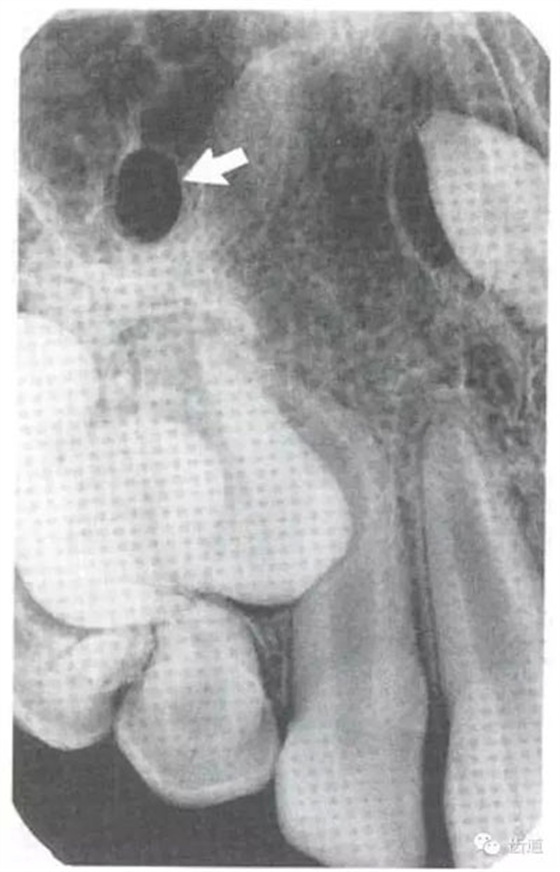

在兩個(gè)中切牙牙根之間或稍上方,多呈橢圓形密度低的影像,切牙孔影像可重疊在一側(cè)中切牙牙根尖處,易誤認(rèn)為根尖周病變,可視牙周膜和骨硬板是否完整加以鑒別

位于前磨牙根尖區(qū)域,為一大致圓形密度低的影像。頦孔位置變異大,多位于第二前磨牙根尖稍下,注意與根尖周病變區(qū)別,其要點(diǎn)是牙周膜及其骨硬板是否連續(xù)不斷。